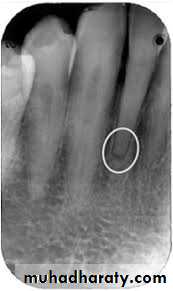

Condensing osteitis is a form of chronic apical periodontitis but it manifests as a radiopacity instead of a radolucency.

It is most commonly associated with teeth that have long-standing pulpitis—usually, or at least initially, chronic reversible pulpitis. Hence, it is essentially an extension of the inflammatory response that began in the pulp or it is an indication that the periapical tissues have been irritated for some time with the result that more bone is laid down rather than being resorbed. The chronic reversible pulpitis may have episodes of acute reversible pulpitis that may be the time when the patient presents for treatment. Alternatively, the chronic reversible pulpitis may develop into chronic irreversible pulpitis, acute irreversible pulpitis or pulp necrosis with infection.

Also, the root canal system may become pulpless and infected. The state of the pulp/root canal will depend on when the patient presents for treatment whereas the increased bone density that is evident radiographically may take many years to resolve and may not resolve at all. When the root canal

system becomes infected, a radiolucency will typically develop immediately adjacent to the root apex and this may be surrounded by the sclerotic bone of the condensing osteitis, thus appearing as both radiopacity and radiolucency.

Radiographic findings—caries may be seen if extensive enough; the periapical region appears more radiopaque than the surrounding bone due to increased bone deposition (i.e., condensing osteitis); some cases may present later after the pulp has necrosed and the root canal system has become infected with various forms of apical periodontitis or apical abscesses—in these cases, some condensing osteitis may still be evident radio-

graphically and there may be a widened PDL space or a radiolucency surrounded by the denser bone of condensing osteitis.